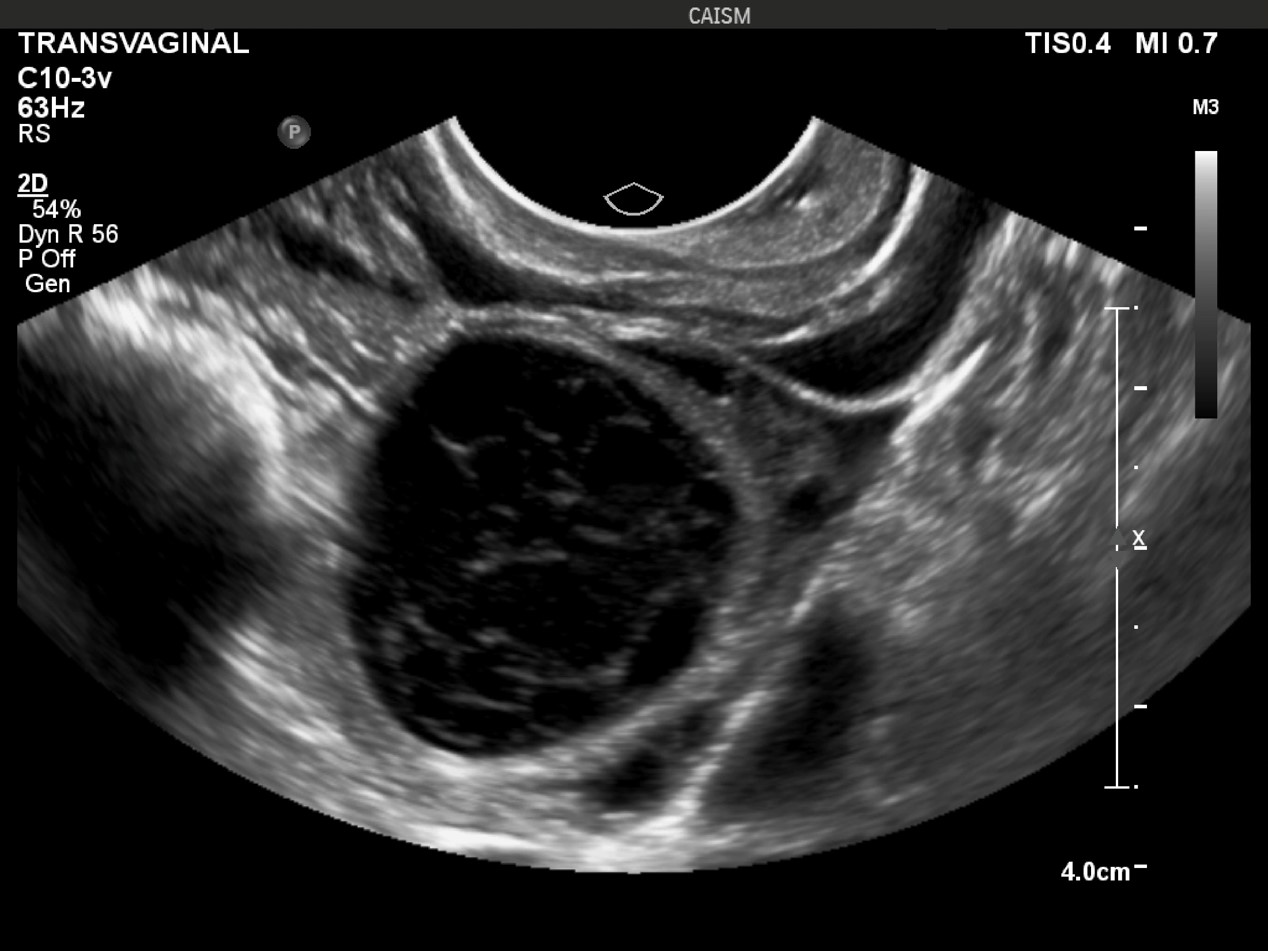

cisto_hemorragico_reticular

Ultrassonografia transvaginal. Observa-se formação cística anexial com conteúdo interno heterogêneo, apresentando finos ecos e padrão reticular (aspecto em “rede”/fibrina), sem componentes sólidos verdadeiros. Achados característicos de cisto hemorrágico ovariano.